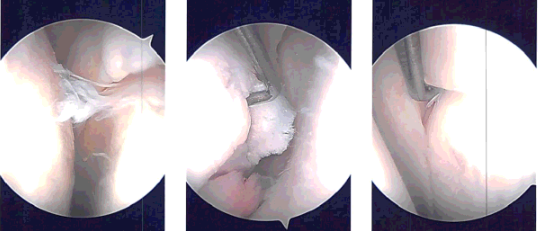

Preoperative antibiotic was already given. A lateral incision was given for the entry portal and the camera was introduced. Examination of the patellofemoral joint showed arthritic changes on the posterior surface of the patella.

Medial compartment examination showed grade 3 to grade 4 osteoarthritic changes on the medial femoral condyle as well as a tear of the anterior horn of the medial meniscus.

Medial portal was made under visualization using a spinal needle. A shaver was introduced and debridement of the anterior horn of the medial meniscus as well as the osteoarthritic lesion and abrasion chondroplasty of the medial femoral condyle was performed. A scope was entered into the intercondylar area where the ACL was found to be intact.

The scope was entered into the lateral compartment where there was diffuse fraying on the medial margin of the lateral meniscus. There was a tear of the anterior horn of the lateral meniscus also. Shaving and debridement of the lateral meniscus was performed using a shaver.

After all of shaving, the camera was introduced in the patellofemoral joint where the grade 3 to grade 4 osteoarthritic changes of the trochlea were observed and abrasion chondroplasty was performed.